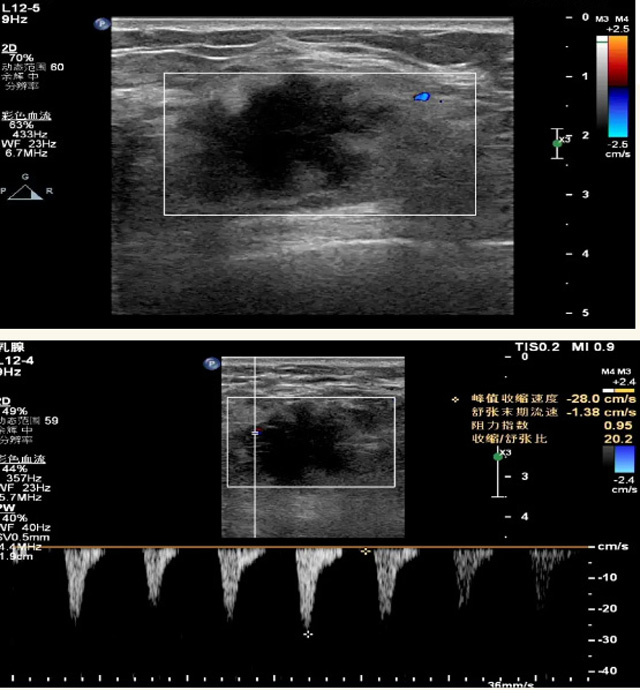

乳腺B超檢查無(wú)輻射,對(duì)囊性病變敏感,可以實(shí)時(shí)觀察病灶。超聲引導(dǎo)活檢跟手術(shù)前的定位。就是它對(duì)于微小的鈣化查出率比鉬靶稍微差點(diǎn)。磁共振MRI檢查也是是沒(méi)有輻射的,對(duì)備孕跟已經(jīng)懷孕的人士比較友好。不用擔(dān)心這個(gè)輻射影響胎兒?jiǎn)栴}。對(duì)乳腺病灶敏感性較高,致密乳腺病灶、乳腺癌的復(fù)發(fā),準(zhǔn)確鑒別囊性及實(shí)性病變??梢詭椭R床醫(yī)生判斷惡性、良性病變。但是MRI磁共振對(duì)微小鈣化不明顯,微鈣化還是鉬靶靠譜點(diǎn)。檢查時(shí)間比較長(zhǎng),有偽影的影響。費(fèi)用相對(duì)B超,鉬靶高很多。

乳腺B超

磁共振MRI

乳腺檢查需要避開(kāi)經(jīng)期,經(jīng)期后一周比較合適。設(shè)備檢查時(shí)候壓10秒鐘左右,不會(huì)有很大的疼痛,稍微有點(diǎn)不適應(yīng)。鉬靶輻射劑量小,腺體越厚,所受劑量也會(huì)有所增高。次診斷性的X線檢查劑量,也達(dá)不到能造成胎兒或者胚胎損傷的劑量。乳腺B超跟磁共振MRI就沒(méi)有輻射。胸小或者假體植入也可以做檢查,乳腺組織曝光野內(nèi),圖像受干擾的情況降到最低,從而保證結(jié)果的準(zhǔn)確性。